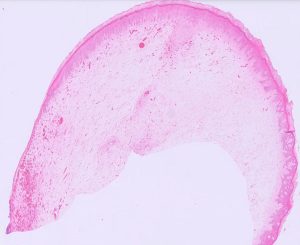

Figure 3: A cross-section of a penile fibropapilloma from a bull showing a proliferation of loosely packed mesenchymal cells, covered by a hyperplastic epithelium.